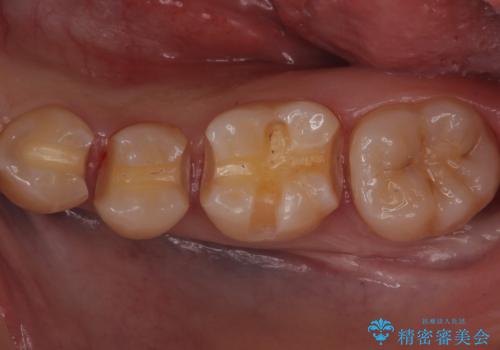

歯と歯の間の虫歯 セラミックインレーでの治療

- 矯正前の虫歯治療です。

歯と歯の間に虫歯があったため適合の良いセラミックインレーで修復処置をしていきました。

歯と歯の間は虫歯の好発部位となっています。

適合の良いインレーでの修復により再発のリスクを下げることができます。